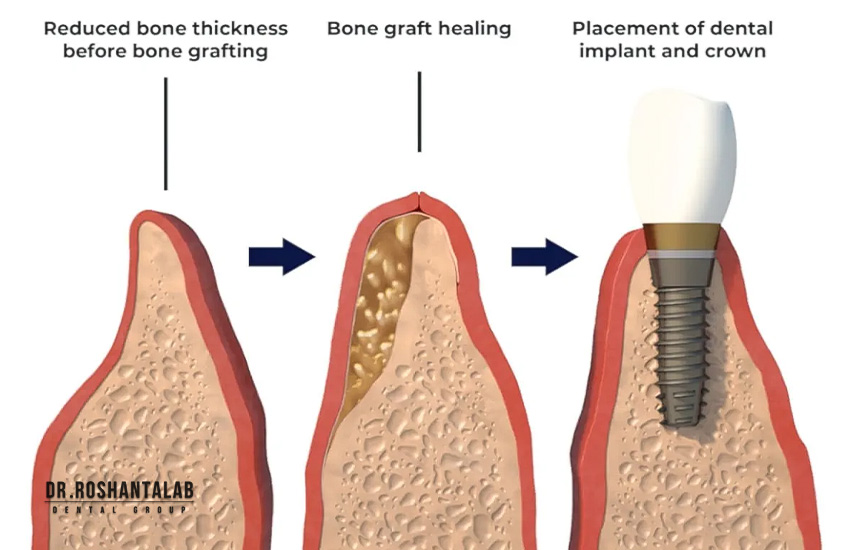

۱. نیاز به پیوند استخوان (Bone Grafting)

ایمپلنت دندان شبیه به پیچی است که باید در دیوار (استخوان) محکم شود. اگر استخوان فک شما در اثر کشیدن دندان در سالهای گذشته، عفونت، یا استفاده طولانیمدت از دندان مصنوعی تحلیل رفته باشد، قطر و ارتفاع کافی برای دربرگرفتن ایمپلنت را نخواهد داشت. در این حالت جراح مجبور است از پودر استخوان (آلوگرافت، زنوگرافت یا استخوان خود بیمار) برای بازسازی فک استفاده کند.

اگر تحلیل جزئی باشد، پیوند همزمان با کاشت ایمپلنت انجام میشود که زمان را خیلی طولانی نمیکند. اما اگر تحلیل شدید باشد (مثلاً عرض استخوان کمتر از ۳ میلیمتر باشد)، ابتدا باید عمل بازسازی استخوان (Ridge Augmentation) انجام شود، ۴ تا ۶ ماه زمان داده شود تا پودر استخوان تبدیل به استخوان زنده شود، و سپس ایمپلنت کاشته شود. این کار پروسه درمان را دو برابر میکند.